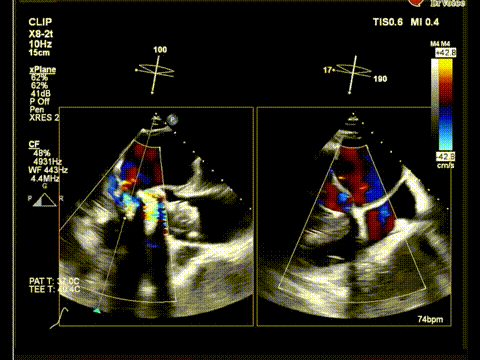

术后食道超声

术后食道超声color